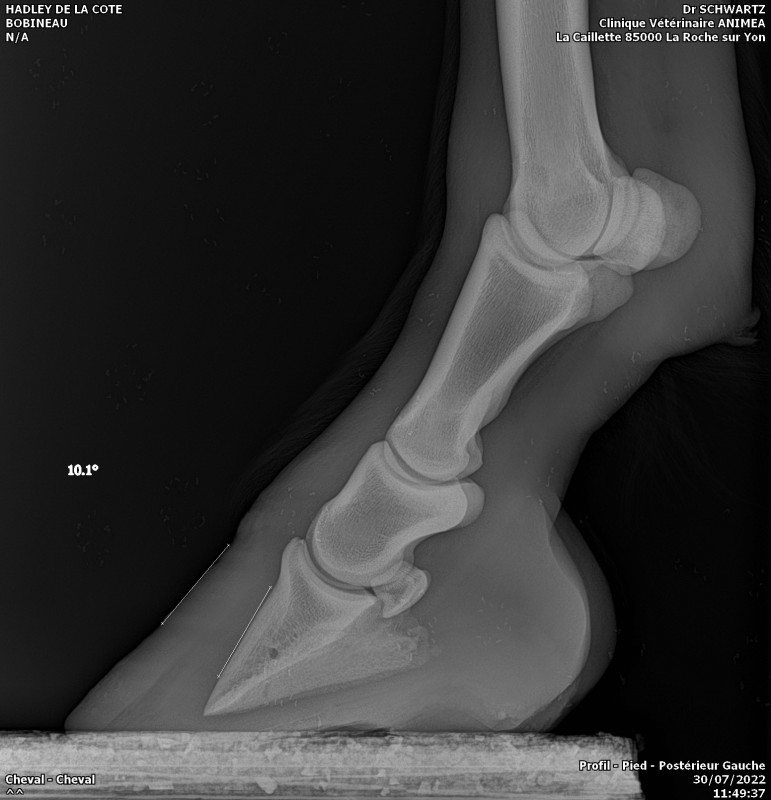

Hadley va bien mieux. Débourrage terminé et sa fourbure qui régresse bien. Les antérieurs sont maintenant ok avec 0 et 1 degrés d'inclinaison. Les postérieurs encore a travailler par le maréchal car il reste 4 et 7 degrés de basculement encore.

Comparaison maintenant/avant

hisatis39 je ne savais pas non plus avant que cela lui arrive. La veto avait preconisé des fers mais conjointement avec le marechal ont a decider de faire sans. C'est plus facile car il faut parer toutes les 3 semaines. idealement, il aurait fallu que je passe un coup de rappe toute les semaines mais avec mon accident aux cotes, je ne pouvais pas. En gros il faut couper en pince, les parois et descendre les talons mais ne pas toucher á la sol qui est fine. La, on a bien recuperer en sol.

Je pense poster sur Facebook en partage publique car on reconnait tous une fourbure des antérieurs mais pas des postérieurs. le cheval est campé dans ce cas. si je n'avais pas insister pour des radios, ..... le pire de tout cela c'est que lorsque j’étais allé la premier fois pour des radios des rotules, le veto avait préconiser de laisser des tallons hauts. sur ceux j'avais demander si cela ne pouvait pas engendrer un basculement des 3eme phalanges. On m'a presque rit au nez. que ce n’était pas vraiment probable sur des postérieurs. Comme quoi, il faut parfois suivre son instinct et non rester sur la théorie..... Bref, le pauvre, cela ne l'a pas aidé!